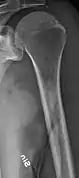

The diagnostic examination of a person with suspected multiple myeloma typically includes a skeletal survey. This is a series of X-rays of the skull, axial skeleton, and proximal long bones. Myeloma activity sometimes appears as "lytic lesions" (with local disappearance of normal bone due to resorption). And on the skull X-ray as "punched-out lesions" (raindrop skull). Lesions may also be sclerotic, which is seen as radiodense.[52] Overall, the radiodensity of myeloma is between −30 and 120 Hounsfield units (HU).[53] Magnetic resonance imaging is more sensitive than simple X-rays in the detection of lytic lesions, and may supersede a skeletal survey, especially when vertebral disease is suspected. Occasionally, a CT scan is performed to measure the size of soft-tissue plasmacytomas. Bone scans are typically not of any additional value in the workup of people with myeloma (no new bone formation; lytic lesions not well visualized on bone scan).

Femur with multiple myeloma lesions

Same femur before myeloma lesions for comparison